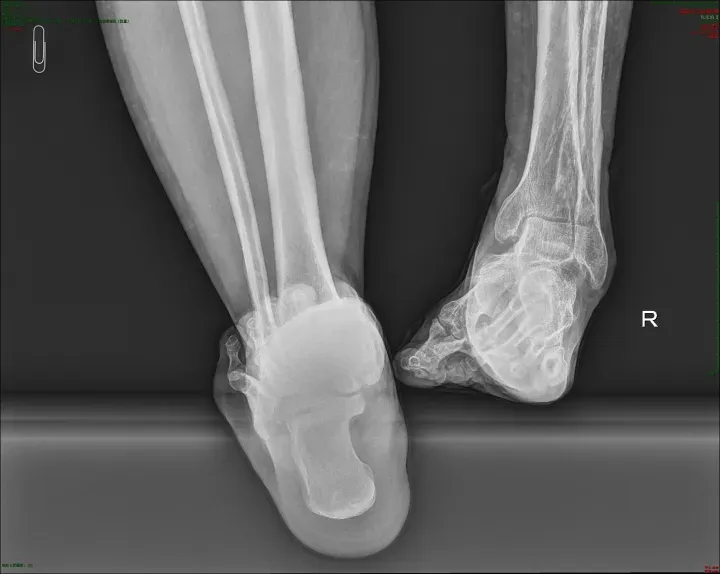

2026年1月,北京积水潭医院郑州医院(郑州市中心医院)创伤骨科与足踝外科接诊了几位从西藏远道而来的特殊患者。患者因外伤导致马蹄内翻足畸形,行走能力严重受损,生活质量备受影响。

此前,他们均因意外外伤引发马蹄内翻足畸形,足部形态异常、步态失衡,不仅日常行走举步维艰,长期的畸形还导致关节劳损、下肢力线紊乱,给身心带来双重折磨。

患者抵达后,我院立即启动绿色就诊通道,组织专业团队为其开展全面检查,通过影像学检测、步态分析等多维度评估,精准掌握畸形程度、骨骼结构及软组织条件,为个性化治疗方案的制定提供了坚实依据。

两院专家共同研读患者病历与检查报告,反复论证治疗方案,最终确定采用计算机辅助泰勒六轴空间外固定架进行矫正治疗。